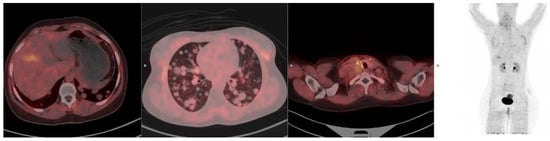

3.7. Lung Cancer

- Novruzov, E.; Mori, Y.; Alavi, A.; Giesel, F.L. The impact of FAP imaging in lung cancer and beyond: A new chapter. Eur. Radiol. 2024, 34, 1946–1947. [Google Scholar] [CrossRef]